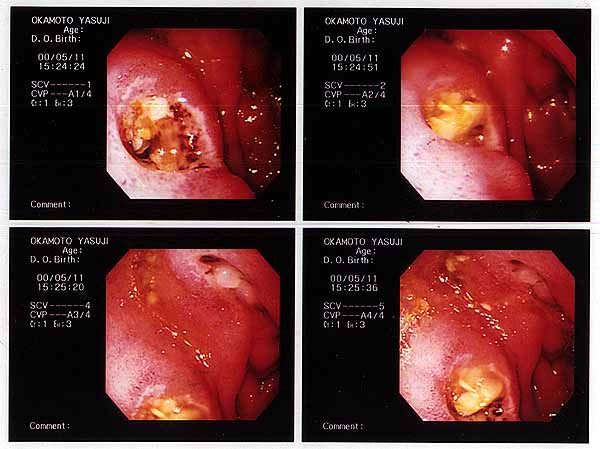

This is a sculpture that I etched with a strong acid.

The acid was a little too powerful, so that it perforated the wall and

leaked with the contents into vulnerable area outside.

That was truly an agonizing work digging into my own deep inside. When completed, I had lost 40 lbs. of my weight

in exchange for this beautiful outcome.

Duodenal Ulcer

title: Perforated Duodenal Ulcer

media: mixed media (duodenum wall tissue, mucus membrane, potato, rice, miso soup)

year: 2000

My name was misread as "Yasuji" here, because of the Chinese characters

with numerous synophones and homonyms.